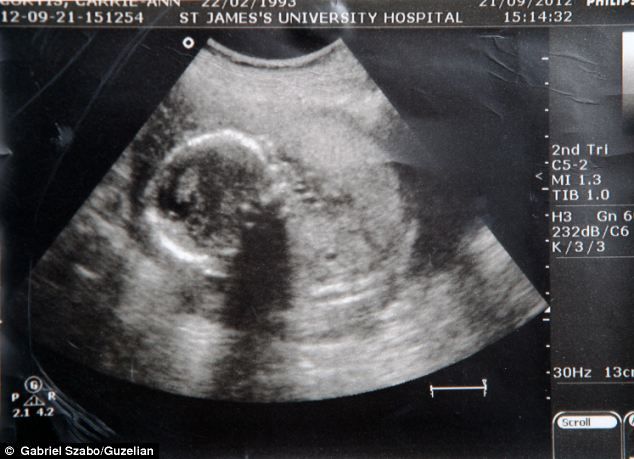

Ο θάνατος του νεογέννητου μωρού, που ήρθε στον κόσμο στην 32η εβδομάδα κύησης, επήλθε λόγω ενός σπάνιου συνδρόμου που ονομάζεται Σύνδρομο του Πότερ το οποίο εμποδίζει την ανάπτυξη νεφρών στο έμβρυο.

Έτσι, ο γιος της νεαρής κοπέλας γεννήθηκε χωρίς νεφρά και έτσι πέθανε λίγα λεπτά αφότου είχε έρθει στον κόσμο.